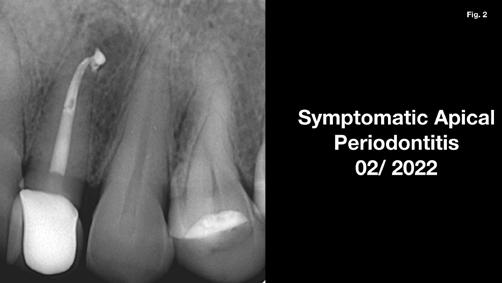

Anyagok és módszerek: 42 éves nő fordult a szerző rendelőjébe tüneti apikális parodontitisszel. A PA röntgenfelvételen az apex körül sugárzástól átlátszó kép és extrudált gyökércsatorna obturációs anyag volt látható, a CBCT-n megőrzött vestibuláris csont mellett (1–2. ábra). Mivel az elmúlt három évben kétszer

végeztek NSRCT-t, és a gyökércsatorna obturáció homogénnek, de túlságosan extrudáltnak tűnt, sebészi kezelés mellett döntöttek.

Szépen beállított ideiglenes korona volt jelen, kóros szondázási mélység és szondázási vérzés nélkül. Nem volt jelen sinus tractus (3–5. ábra). Tüneti apikális parodontitis 1. osztály (Von Arx&Cochrane 2001); B osztály (Kim&Kratchman 2005) és korábban elvégzett gyökérkezelés volt a végső diagnózis.